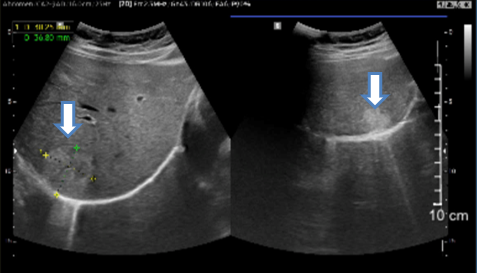

- Chụp cắt lớp vi tính ổ bụng:

Hình 1: Cắt lớp vi tính ổ bụng (09/06/22): Hình ảnh nhiều khối ngấm thuốc bàng quang (mũi tên) – Theo dõi u bàng quang đa ổ

Hình 2: Cắt lớp vi tính ổ bụng (09/06/22): Hình ảnh 2 khối u máu gan ở hạ phân thùy VII-VIII kích thước lần lượt là 35x38mm và 19x20mm (mũi tên)